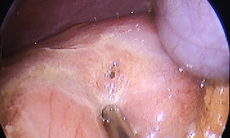

Bác sĩ tiến hành phẫu thuật loại bỏ khối u nang lớn trong bụng cháu bé.

Trong quá trình phẫu thuật, các bác sĩ xác định đây là khối u nang lớn nằm sau phúc mạc (phúc mạc còn gọi là màng bụng, là lớp màng bao phủ mặt trong thành bụng và bọc các cơ quan trong ổ bụng như gan, dạ dày, ruột…).

Khối u khiến toàn bộ đại tràng phải bị đẩy lệch vào giữa ổ bụng, nằm sát các cấu trúc quan trọng vùng sau phúc mạc như thận, niệu quản và bó mạch chậu phải. Ê-kíp phẫu thuật đã tiến hành bóc tách cẩn trọng, giải phóng các cấu trúc và cắt bỏ hoàn toàn khối u nang.